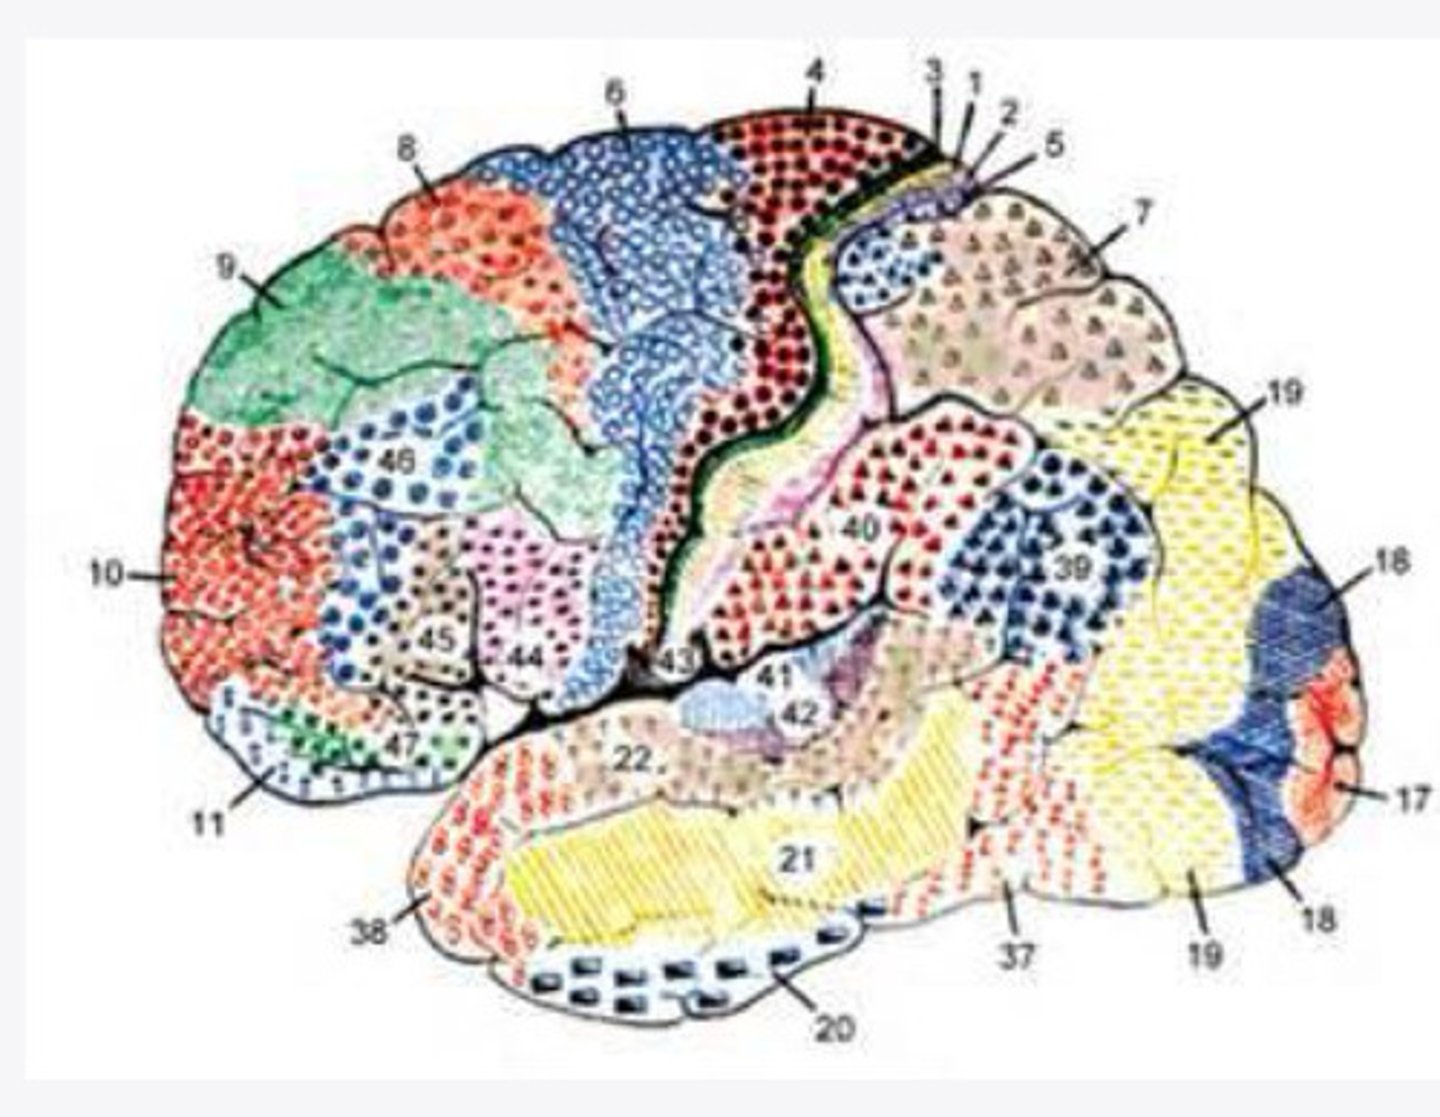

52 Brodmann areas

What are the histological divisions of the cortex of the brain?

cerebral cortex on the basis of histological sections

What did Brodmann study?

52 distinct regions of the cortex based on the thickness of cell layers alone

What did Brodmann find?

2-5

What layers of the cortex of the brain did Brodmann find were variable in histological sections?

function

In the 52 Brodmann areas, structure lens itself to ______

4, 6, 8, 44/45

What are the important Brodmann areas of the frontal lobe?

motor movements

What is the function of Brodmann area 4?

2 and 5

What layers of the cortex are thick in Brodmann area 4?

helps coordinate activity in the motor cortex (opposing muscle groups)

What is the function of Brodmann area 6?

2 and 3

What layers of the cortex are thick in Brodmann area 6?